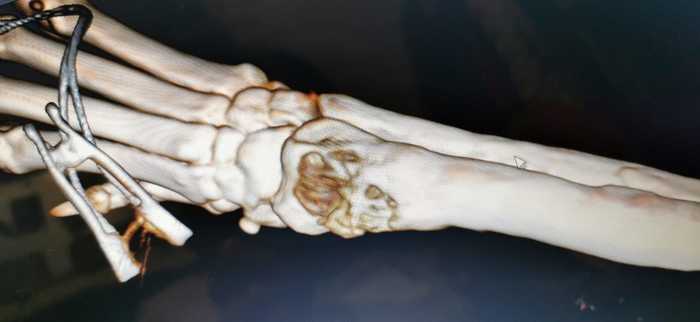

Срез лапы зажил, края стянулись и не выглядели уже страшно, ну или я пригляделась уже. В один из зимних дней, я наблюдала за этим кабаном по камерам, он как раз вот этот вот заборчик перешагнул и пошел гулять по палисаднику, а там сугробы, уже начали подтаивать и снег стал очень хрупким и глубоким. Смотрю, что то он как то странно ходит. Выглянула в окно, и, кроме мата ничего и не смогла родить. Произошло вот что.

Надо сказать, что тут никто и не виноват, просто стечение обстоятельств. Умка поднабрал после операции, плюс снег, сугробы и его упертость алабаичья. Вот надо ему ходить по сугробам и все, пошел. Я низ задолбалась искать, выскочила в домашнем на улицу, и бегала в тапках по сугробам. Нафига правда не ясно. Скорее всего бабская хрень какая то в голове сработала, надо было найти зачем то, потом муж нашел, я не смогла.